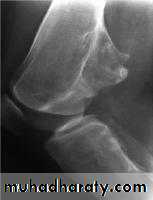

Osteochondroma

= exostosisCommonest benign bone tumour

It is bone outgrowth covered by cartilageHereditary multiple exostosis : AD